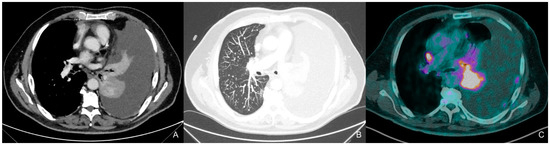

2. Case Description